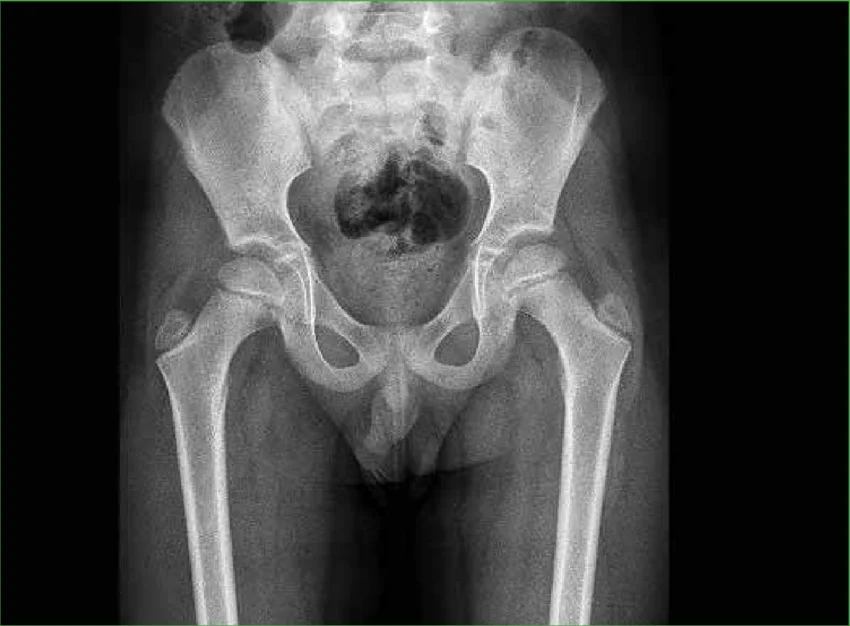

La radiografía de cadera es un examen de diagnóstico por imagen que emplea rayos X para generar una representación detallada a través de las estructuras internas de los tejidos blandos, huesos de la pelvis y las articulaciones de la cadera.

El proceso implica el uso de un generador de rayos X que emite un haz de radiación dirigido hacia la cadera. Los huesos, al ser más densos, absorben más radiación y aparecen en blanco, mientras que los tejidos blandos, que permiten el paso de los rayos, se muestran en tonos más oscuros, lo que permite evaluar la anatomía interna y detectar alteraciones.

Al capturar imágenes claras de la articulación y los huesos circundantes, la radiografía permite a los profesionales de la salud identificar posibles causas de dolor, limitación de movimiento o inflamación.

La radiografía de cadera es un examen de imagenología crucial para diagnosticar la causa de síntomas comunes como dolor, hinchazón, cojera, sensibilidad o deformidades en la zona de la cadera. A través de este estudio, los médicos pueden detectar fracturas óseas, luxaciones articulares y otros daños estructurales que afectan el correcto funcionamiento de la cadera.

Además, ayuda a identificar la presencia de quistes, tumores óseos o infecciones que afectan esta zona del cuerpo. Asimismo, permite detectar diversas enfermedades y afecciones crónicas o degenerativas, como la artritis, garantizando una vigilancia continua y adecuada del estado de los huesos y articulaciones del paciente..